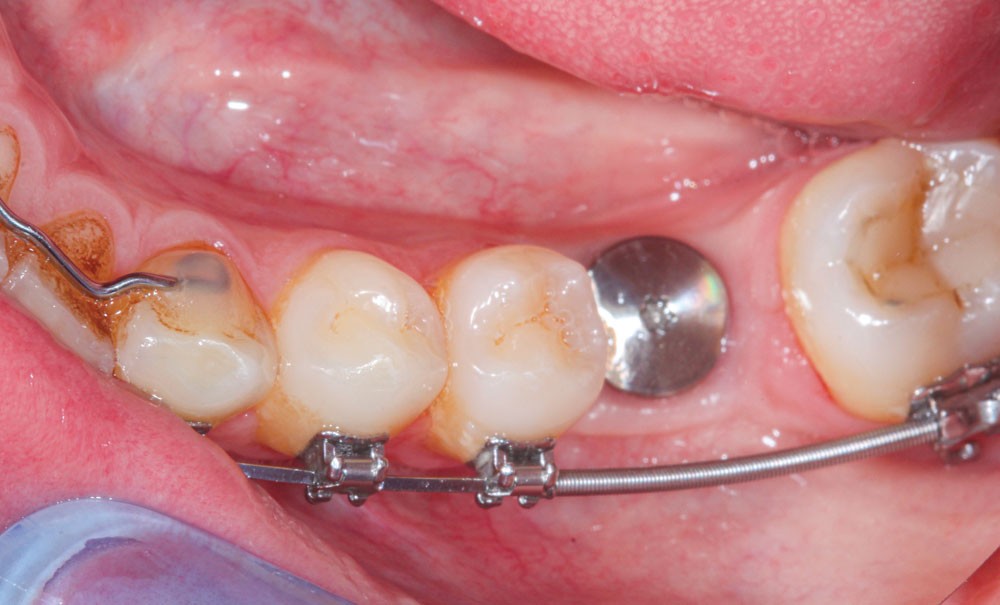

Cette version, quand elle se produit, modifie les espaces interdentaires et complique l’hygiène proximale des patients. Des caries peuvent alors se développer en interproximal sans que cela soit forcément visible à l’examen visuel (fig. 3 et 4). Les radios de type bite-wing (rétro-coronaires) prennent alors tout leur sens (fig. 5 et 6).